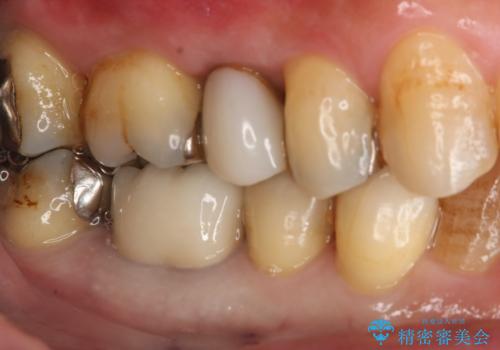

保険材料をセラミックにやり変えたい セラミックインレー

- 保険で治療された右下5番をセラミックにやり変え希望の患者様です。

切削量などを考慮し、セラミックインレーでの治療を選択しました。

古い材料と虫歯を全て除去した上で形成・印象を行い、セラミックインレーを装着しています。